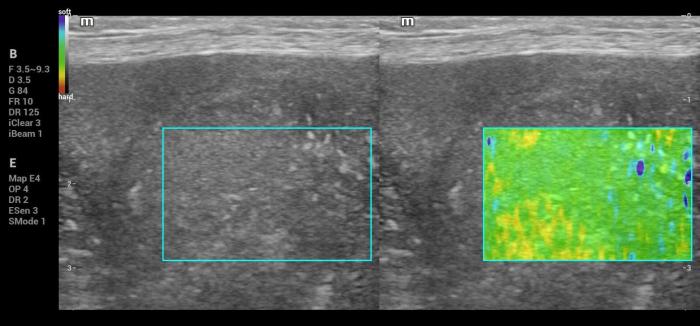

Además de la medición cuantitativa de la velocidad de la onda de corte expresada en metros por segundo (m/s), el sistema Natural Touch Elastography® (Mindray MX7) dispone de una función complementaria de representación cualitativa y semicuantitativa de la rigidez tisular (Figura1-4). Esta herramienta permite asignar valores numéricos y porcentajes relativos al grado de dureza o blandura del tejido evaluado y facilita la comparación visual y numérica entre diferentes regiones de interés dentro de un mismo órgano, incluyendo la relación entre una lesión focal y el parénquima esplénico adyacente.

De acuerdo con la documentación técnica del fabricante, esta funcionalidad se basa en el análisis de la respuesta tisular al impulso acústico y en algoritmos de seguimiento por radiofrecuencia, lo que contribuye a una evaluación intraorgánica más precisa. Si bien estos valores no sustituyen las mediciones cuantitativas en m/s ni cuentan con puntos de corte validados para la diferenciación diagnóstica, su utilización aporta información complementaria útil para la interpretación clínica de los hallazgos elastográficos, especialmente cuando se integra con la evaluación en modo B y Doppler.

Hallazgos elastográficos (Natural Touch Elastography®): la lesión mostró una rigidez similar al parénquima esplénico circundante, con valores que no superaban los rangos normales descritos para bazo canino3,4 (Figura 9-10). La uniformidad de las mediciones, sin artefactos relevantes y con estabilidad entre adquisiciones consecutivas, aumentó la confiabilidad de la evaluación.